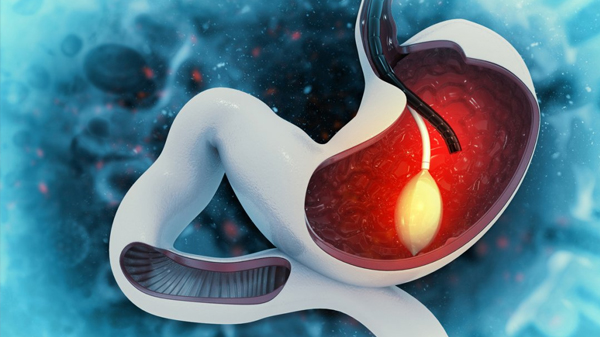

La inserción de balón gástrico es un procedimiento médico no quirúrgico que se utiliza para ayudar a las personas con obesidad a perder peso. Durante el procedimiento, se inserta un balón de silicona lleno de solución salina en el estómago a través de la boca utilizando un endoscopio. El balón se llena con solución salina para que ocupe espacio en el estómago y así reducir la cantidad de alimentos que una persona puede consumir antes de sentirse llena.

El procedimiento se realiza bajo sedación para reducir la incomodidad del paciente y suele durar alrededor de 20-30 minutos. Una vez que se coloca el balón, el paciente debe seguir una dieta y un programa de ejercicios supervisados para ayudar a maximizar la pérdida de peso. El balón se retira después de 6 a 12 meses después de su colocación.

La inserción de balón gástrico no es una solución a largo plazo para la obesidad y solo se recomienda para personas con un índice de masa corporal (IMC) entre 30 y 40 que han intentado sin éxito perder peso a través de cambios en la dieta y el ejercicio. También puede ser recomendado como una solución temporal para personas que necesitan perder peso rápidamente antes de someterse a una cirugía de pérdida de peso.

En resumen, la inserción de balón gástrico es un procedimiento médico no quirúrgico que se utiliza para ayudar a las personas con obesidad a perder peso. Durante el procedimiento, se inserta un balón de silicona lleno de solución salina en el estómago para reducir la cantidad de alimentos que una persona puede consumir antes de sentirse llena. El procedimiento se realiza bajo sedación y se retira después de 6 a 12 meses. Se recomienda solo para personas con un IMC entre 30 y 40 que han intentado sin éxito perder peso a través de cambios en la dieta y el ejercicio.